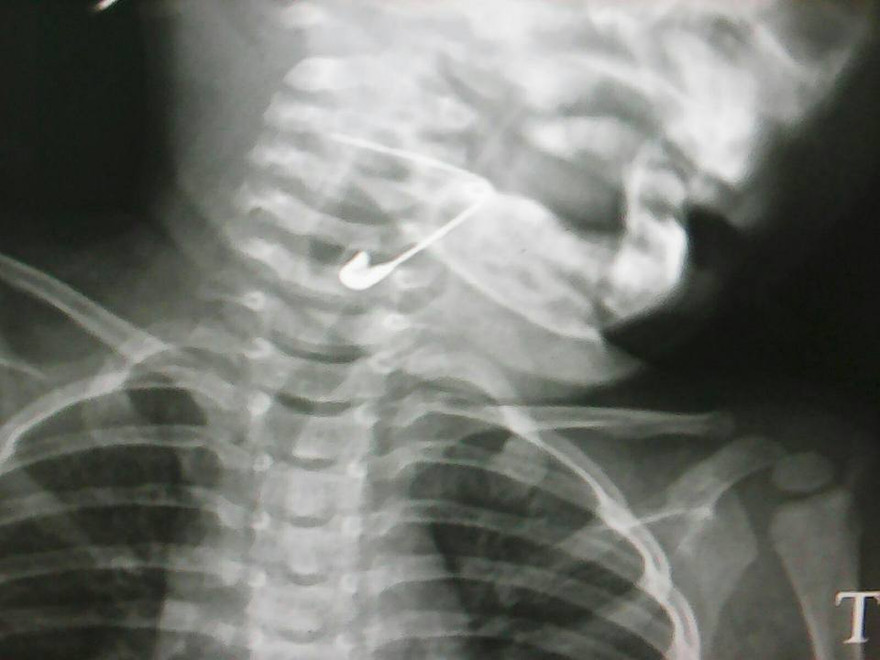

Cây kim băng được phát hiện trong thanh quản cháu bé trong tư thế mở

Trước đó, lức 10h30 phút cùng ngày, bệnh viện tiếp nhận tiếp nhận cháu Nguyễn Lê Hoàng V. (18 tháng tuổi, tạm trú xã phường Điện Nam Bắc, thị xã Điện Bàn) trong tình trạng mệt khó thở, buồn nôn. Người nhà cho biết trong lúc đang chơi đùa cháu V. nuốt phải cây kim băng nên vội đưa cháu tới bệnh viện. các y, bác sĩ thăm khám và phát hiện một cây kim băng trong thanh quản. Các bác sỹ nhận định, cây kim trong tư thế mở nên việc lấy ra phải hết sức thận trọng. Các bác sỹ tiến hành nội soi họng gắp lấy cây kim ra ngoài.